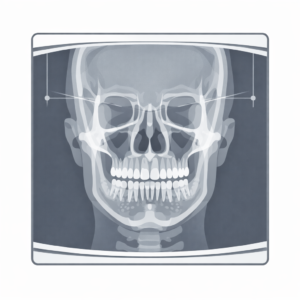

パノラマレントゲン

歯の状態、歯を支える骨、親知らず、埋まっている歯、治療済みの歯の状況などを俯瞰的に把握します。

歯科用CBCT(コーンビームCT)

顎・歯・歯槽骨・顎関節などを3次元で評価できます。埋伏歯や骨の状態、顎関節評価など、必要性がある場合に有用です。